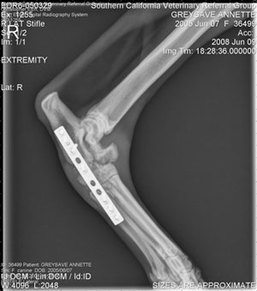

The reason hocks heal so well with so few repercussions is that the usual fracture is a slab

fracture of a tiny (<1") bone (central tarsal bone) in a non-moving joint. Sometimes, more

than one of these tiny tarsal bones is involved - there are 5 of them, plus the larger talus and

calcaneus bones making up the hock joint. Since the fracture is in a non-moving joint to begin

with, the arthritis that develops around the site is fairly insignificant to the dog's movement.

And it takes movement to cause pain.

There are a few more disastrous hock fractures, such as when the tip of the calcaneous bone

(tip of the hock) breaks off and the dog's Achilles tendon goes with it. This is a dog that really

- Dateianhänge

- hock1.jpg (36.91 KiB) 2178 mal betrachtet

- hock.jpg (14.65 KiB) 2179 mal betrachtet

- hock2.jpg (38.88 KiB) 2179 mal betrachtet